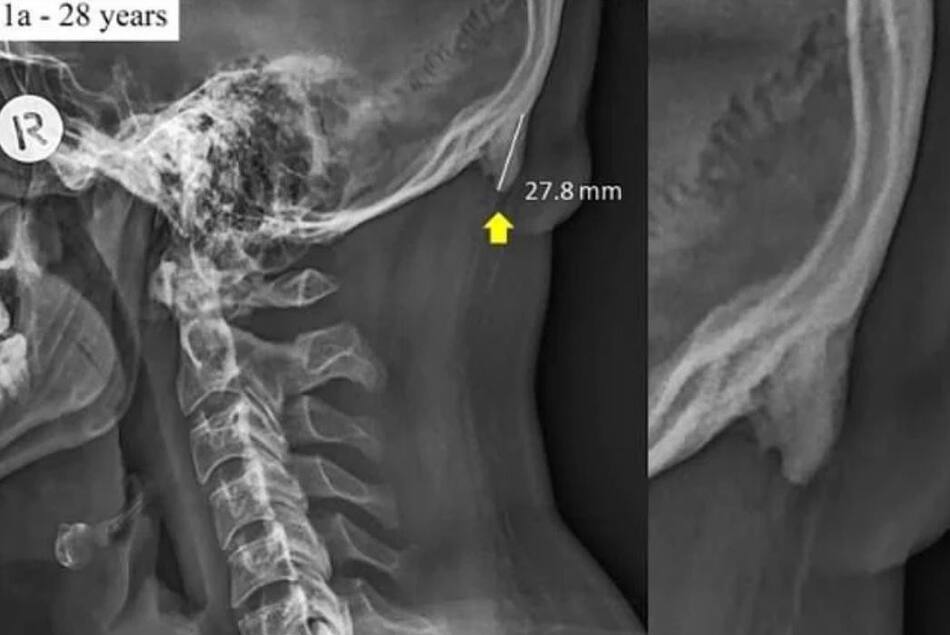

La estructura ósea trata de adaptarse para sostener mejor nuestra cabeza. La prueba está en las imágenes de rayos X publicadas por investigadores australianos. La cabeza de adulto promedio puede pesar alrededor de 5 kilogramos.

Los crecimientos llamados protuberancias occipitales externas agrandadas, se encuentran en la parte inferior del cráneo.